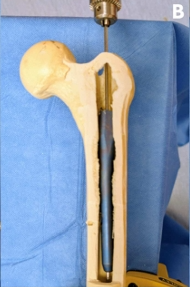

髓内钉断裂后,将插入端(如顺行股骨髓内钉的近端或逆行钉的远端)称为可触及部分,另一端则为难以触及部分(如顺行钉的远端或逆行钉的近端)。

本技术所需设备见表1。应用前提是:断裂部分至少保留一个完整的圆形锁定孔,且孔内最好仍有锁定螺钉(图2A)。若无可用锁定孔,需徒手钻取远端锁定孔。

理想情况下应保留髓内钉整体在骨内,避免分段取出,因断裂部分将随主体一同拔出而不易卡顿。若无法实现,可扩髓至比钉直径大1毫米,以利取出(非必需)。

用2-0缝线系住微型螺钉头部以防脱落,在透视引导下将其旋入或敲入锁定孔(图2C)。螺钉就位后回抽导丝,使其与螺钉嵌合(图2D),随后敲击T形手柄将导丝连同断裂髓内钉一并取出(图2E)。操作中需持续保持导丝张力,以防螺钉脱落。关键步骤见表2,技术细节见补充视频。